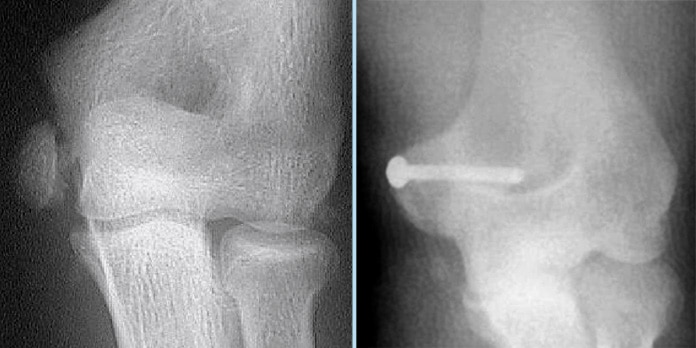

Fracture épitrochlée

Réduction au bloc et ostéosynthèse impérative.